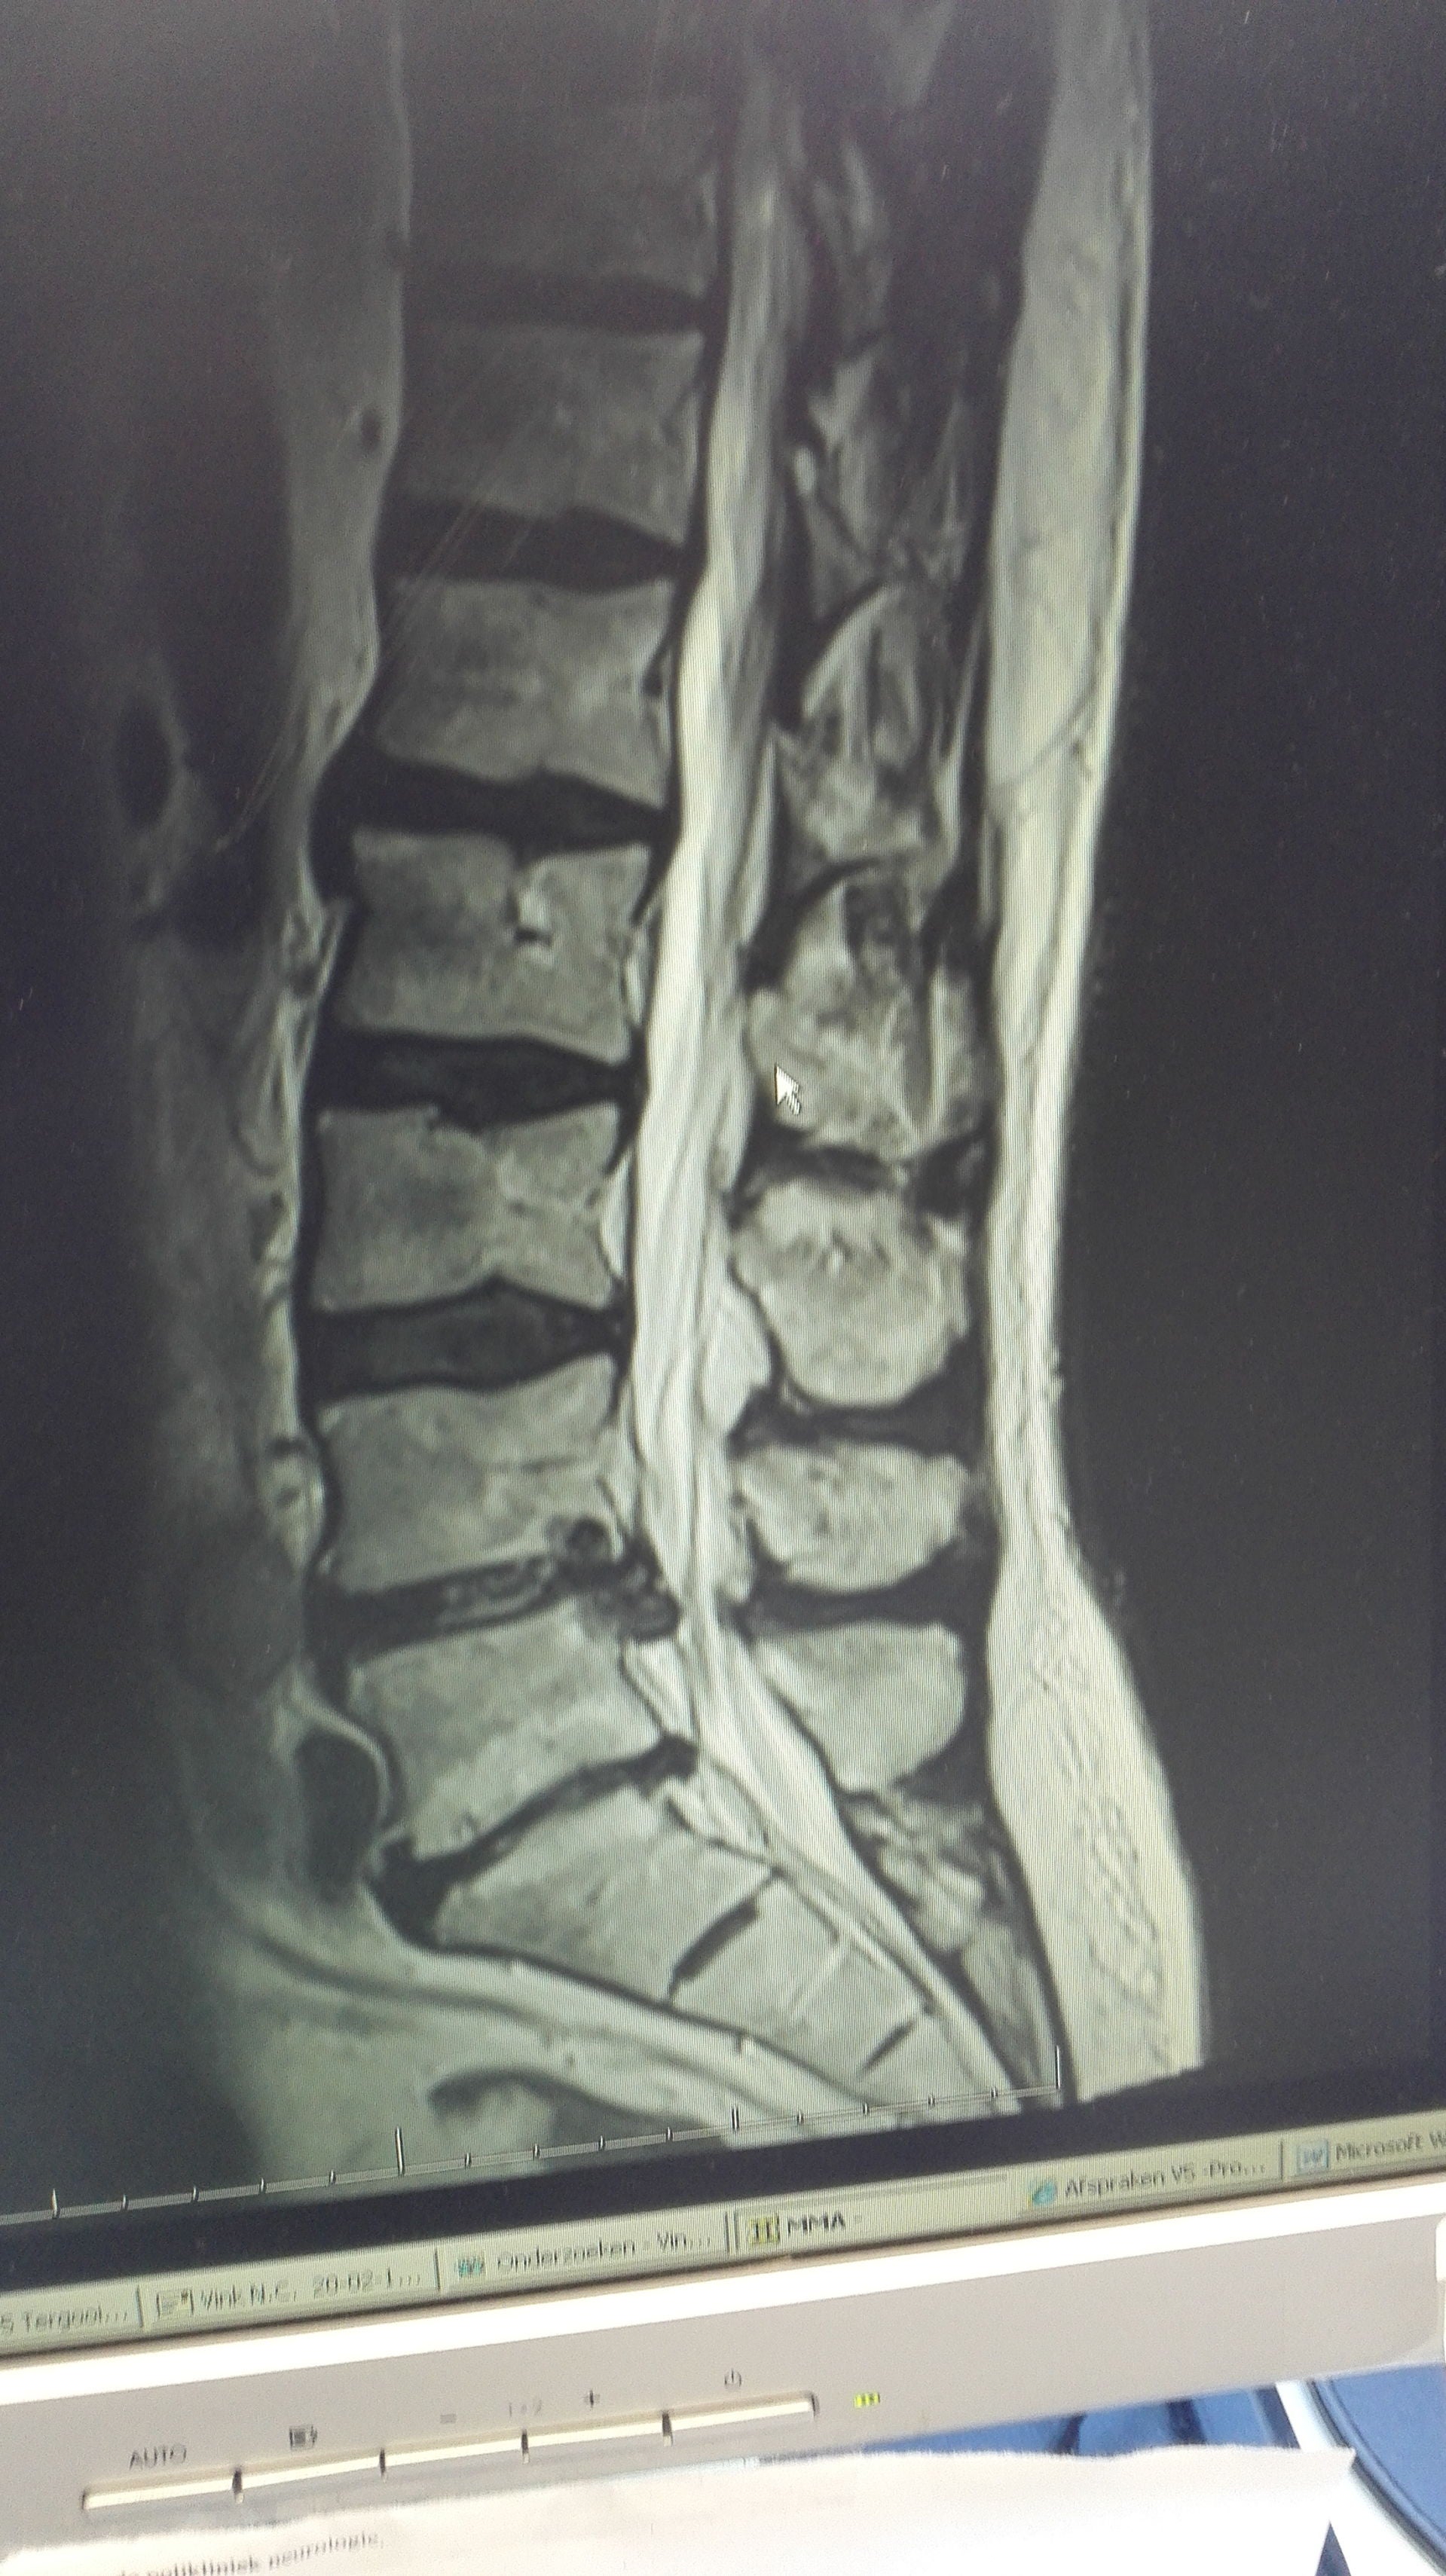

Dat een hernia zo loopt langs je benen